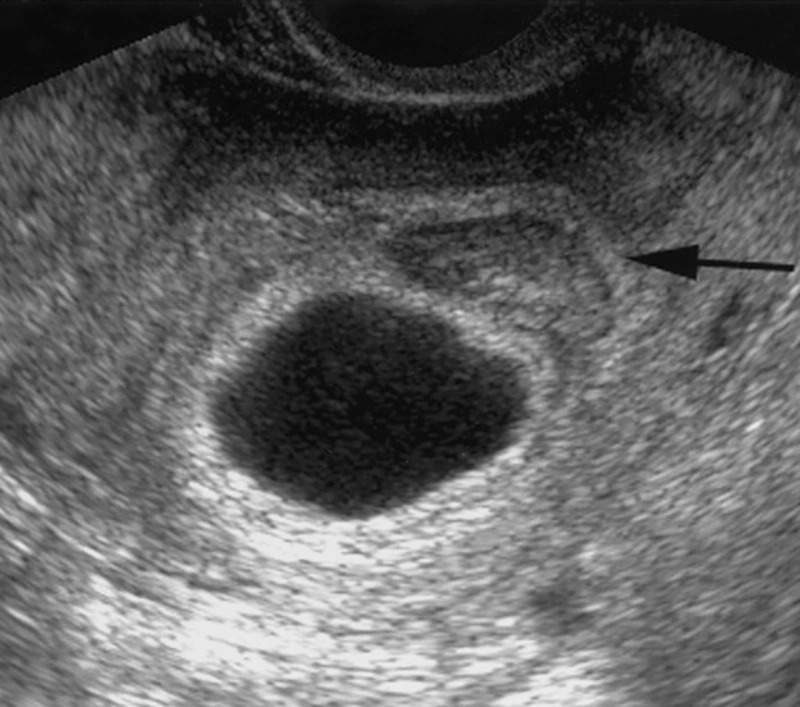

Kích thước túi thai

Ảnh trên: Túi thai

Thai trống (Blighted Ovum)

Blighted Ovum

Ảnh trên: Thai trống (Blighted Ovum)

Thai trống, hay còn gọi là mang thai không phôi, xảy ra khi trứng đã thụ tinh làm tổ trong tử cung nhưng không phát triển thành phôi thai. Mặc dù phôi không tồn tại, túi thai và nhau thai vẫn có thể phát triển trong một thời gian ngắn, gây ra các triệu chứng mang thai và kết quả thử thai dương tính do nồng độ hCG tăng.

Trên siêu âm, bác sĩ sẽ thấy túi thai phát triển nhưng bên trong rỗng, không có túi noãn hoàng hoặc phôi thai. Túi thai có thể tiếp tục lớn lên, nhưng khi đạt đến một kích thước nhất định (thường là >25mm theo tiêu chuẩn ACOG) mà vẫn không có phôi, chẩn đoán thai trống sẽ được xác định.